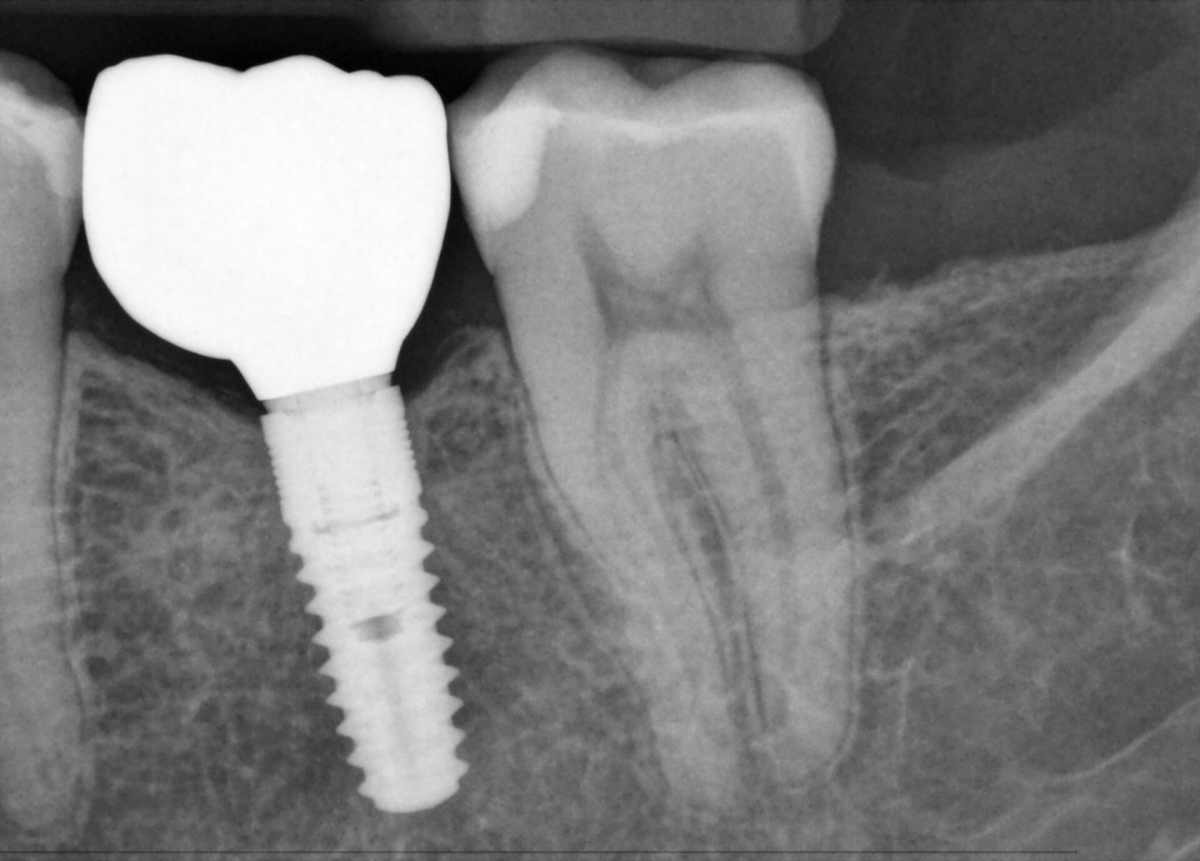

Xios AEセンサーは、優れた画質と高度なフィルタリング機能により、解剖学的構造を強調し、正確で詳細な診断を可能にすることで、高い臨床性能をサポートします。歯内療法や虫歯などの適応症において、低ノイズの画像、細部の視認性の向上、専用のフィルタリングは、診断の確実性に関連する優位性を提供し、治療評価における真の信頼性を高めるのに役立ちます。ハードウェアとSidexis 4ソフトウェアのスマートな接続性と組み合わせることで、あらゆる診療所にとってフレキシブルなパートナーとなります。